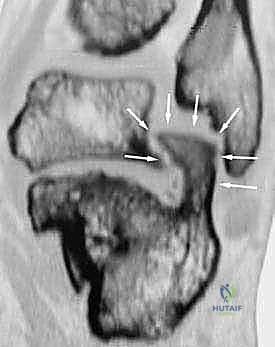

- الأشعة المقطعية ثلاثية الأبعاد (3D CT Scan): وهي الخطوة الذهبية والأهم في عيادة الدكتور هطيف. تتيح هذه الأشعة بناء نموذج ثلاثي الأبعاد دقيق للكعب المشوه، مما يسمح بتحديد أماكن الانحشار العظمي بدقة المليمتر، ومعرفة مدى تلف الأسطح المفصلية. بناءً على هذه الصور، يتم وضع خطة "القطع العظمي التصحيحي" قبل دخول غرفة العمليات.